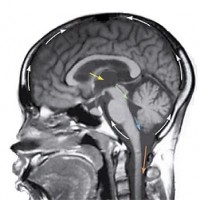

Een waterhoofd wordt veroorzaakt door een overmatige hoeveelheid hersenvocht (cerebrospinale vloeistof) in de hersenholten. Het probleem is dat dit hersenvocht niet wordt opgenomen, of dat de opname langzamer verloopt dan normaal. Het vocht omgeeft de hersenen en loopt in de hersenen door het ventrikelsysteem en andere hersenholten.

Het hersenvocht wordt normaal in een constant tempo aangemaakt. Omdat het in de bloedbaan wordt opgenomen blijft de totale hoeveelheid vocht ongeveer 150 ml. Bij hydrocefalie is deze hoeveelheid echter veel groter.

De beenderen welke de hersenen en het ruggenmerg insluiten vormen een gesloten holte met een beperkt volume. Elke toename van de hoeveelheid weefsel of vloeistof in deze gesloten ruimte, leidt tot een verhoging van de druk. Als het volume hersenvocht toeneemt, stijgt de intracraniale druk. Daardoor worden de ventrikels vergroot en het hersenweefsel samengedrukt. Het zijn deze veranderingen die de symptomen van hydrocefalie veroorzaken.

Soms kan een waterhoofd al worden gezien wanneer er tijdens de zwangerschap een echo wordt gemaakt. Vaak wordt je dan doorverwezen naar een arts in een gespecialiseerd ziekenhuis waar ook gespecialiseerde echo-apparatuur aanwezig is. Meestal worden er röntgenfoto's van de schedel gemaakt. Soms worden er ook scans (CT- en MRI-scan) gemaakt van de hersenen. Men maakt gebruik van geluidsgolven om de ventrikels bij een baby zichtbaar te maken.